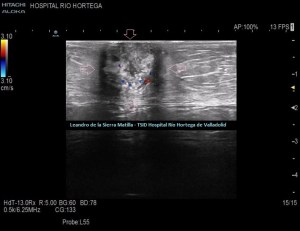

Cambiamos a una sonda lineal para un estudio más detallado, observando una LOE hipoecogénica con zonas híper-isoecogénicas, heterogénea, sólida, sin contenido de asas intestinales ni de grasa, con bordes mal definidos y con flujo doppler en su interior, ubicada dentro de la cavidad umbilical (FIGURAS 5, 6 Y 7)

5

6

7